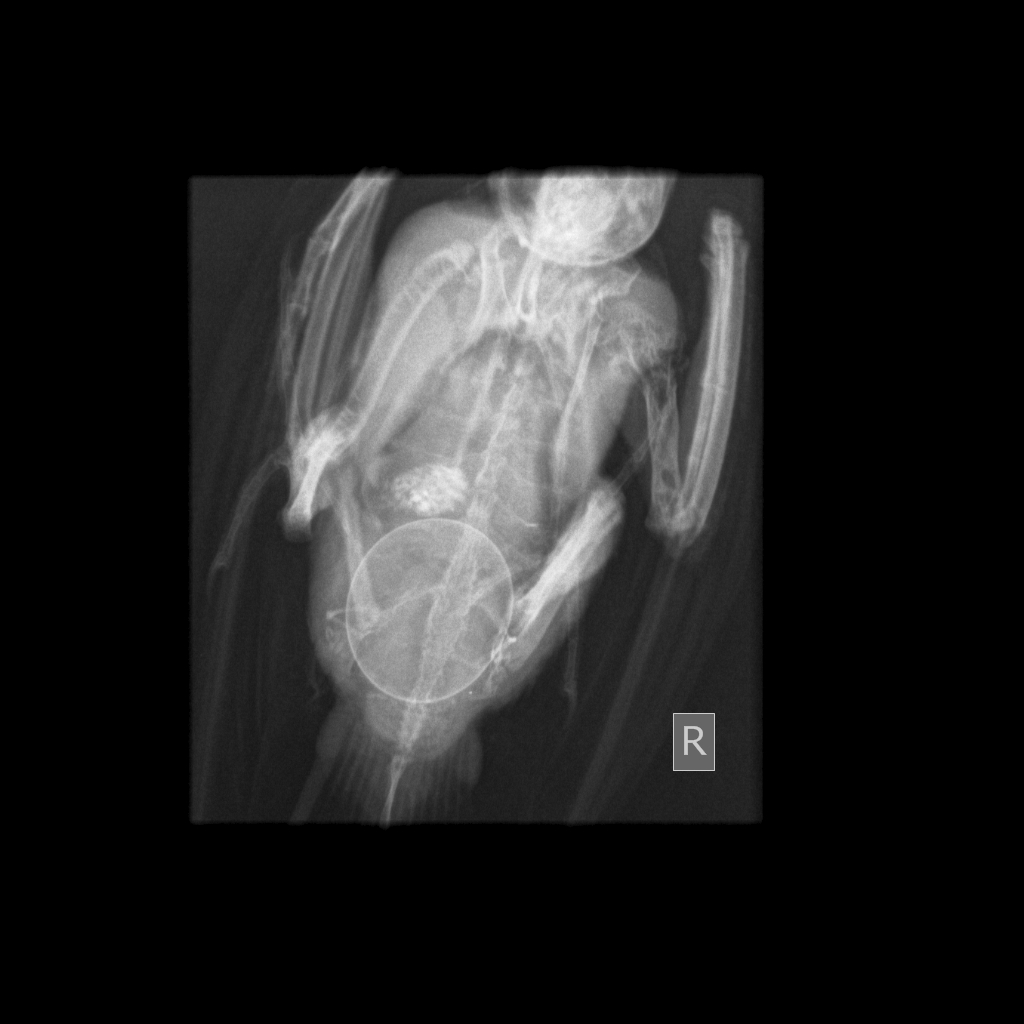

X-rays revealed not 1 but 2 eggs stuck (no wonder she was so poorly!). Thankfully with fluid therapy, calcium, pain relief and medications to help stimulate contracture of the oviduct she managed to lay an egg on the way back (though according to Julie this was likely aided by the G-force of some particularly pacy cornering by the driver!)

Once she had laid this egg, much to John and Julie’s delight, she was again able to pass her droppings normally and her demeanour and appetite improved dramatically……….. however, we knew one pesky egg still remained.

As she was now stable, we decided Percy was fit to travel up to Cheshire and after thanking Tom for his life saving efforts, we saw her when to all intents and purposes she appeared back to normal and we wondered if she had secretly managed to get rid of the second one? Sadly not, as palpation and a second x-ray confirmed.